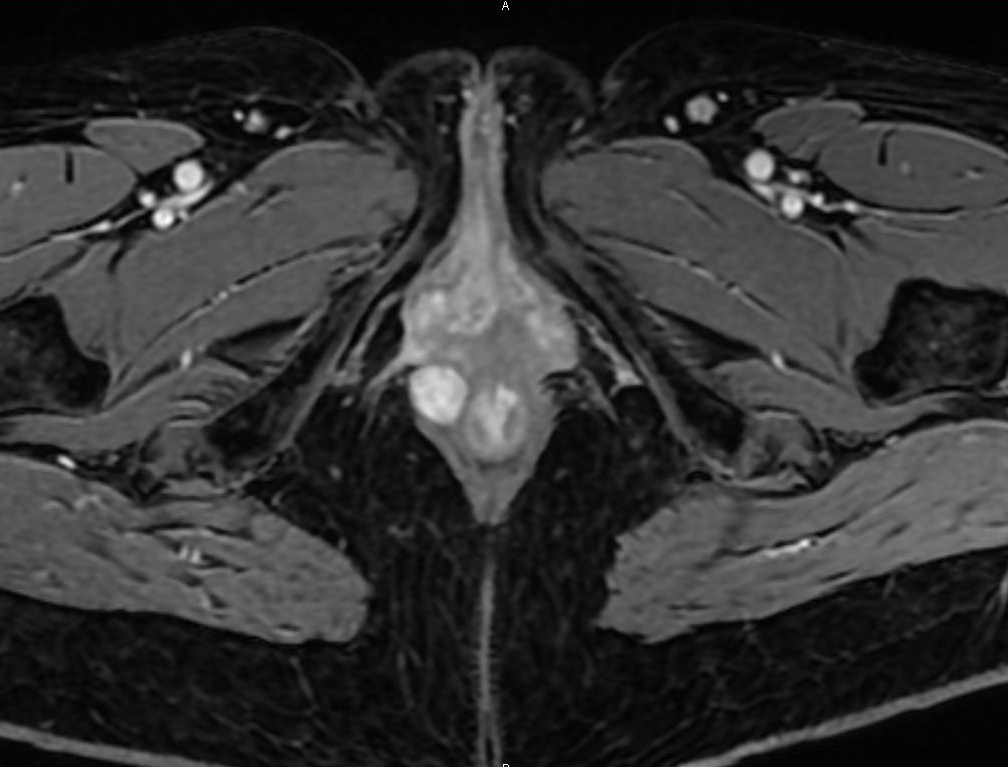

Souvent asymptomatique, cette tumeur peut provoquer une sensation de corps étranger ou une gêne à la défécation. Elle est parfois découverte de façon fortuite, lors d’une endo­scopie ou d’une chirurgie, par exemple. La masse est ferme, bien limitée, souvent mobile à l’examen clinique. L’imagerie par endosonographie et/ou IRM (fig. 2) permet de préciser les rapports avec le sphincter et d’éliminer un léiomyosarcome (aspect hétérogène, envahissement, nécrose).